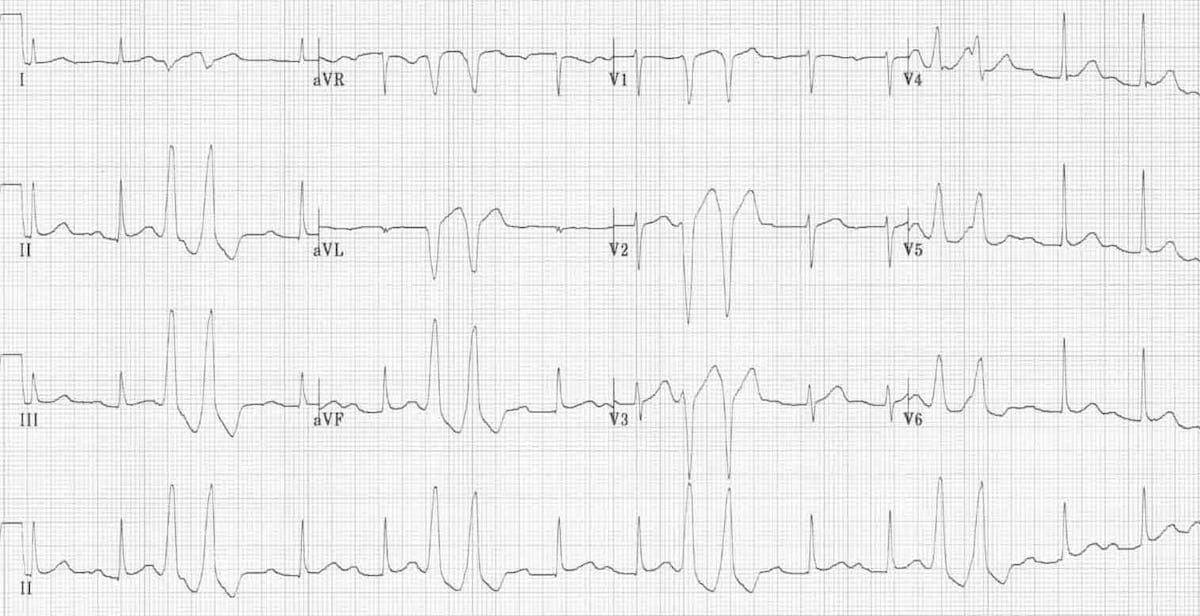

This ECG shows hyperkalaemia. Tall, tented T waves are best seen in V2-V5. There are no identifiable P waves and the QRS is starting to widen.

© Life in the Fast Lane. Licensed under CC BY-NC 4.0

This ECG shows very severe hyperkalaemia, with tall, tented T waves, and severe QRS widening, resembling a sine wave.

© Life in the Fast Lane. Licensed under CC BY-NC 4.0